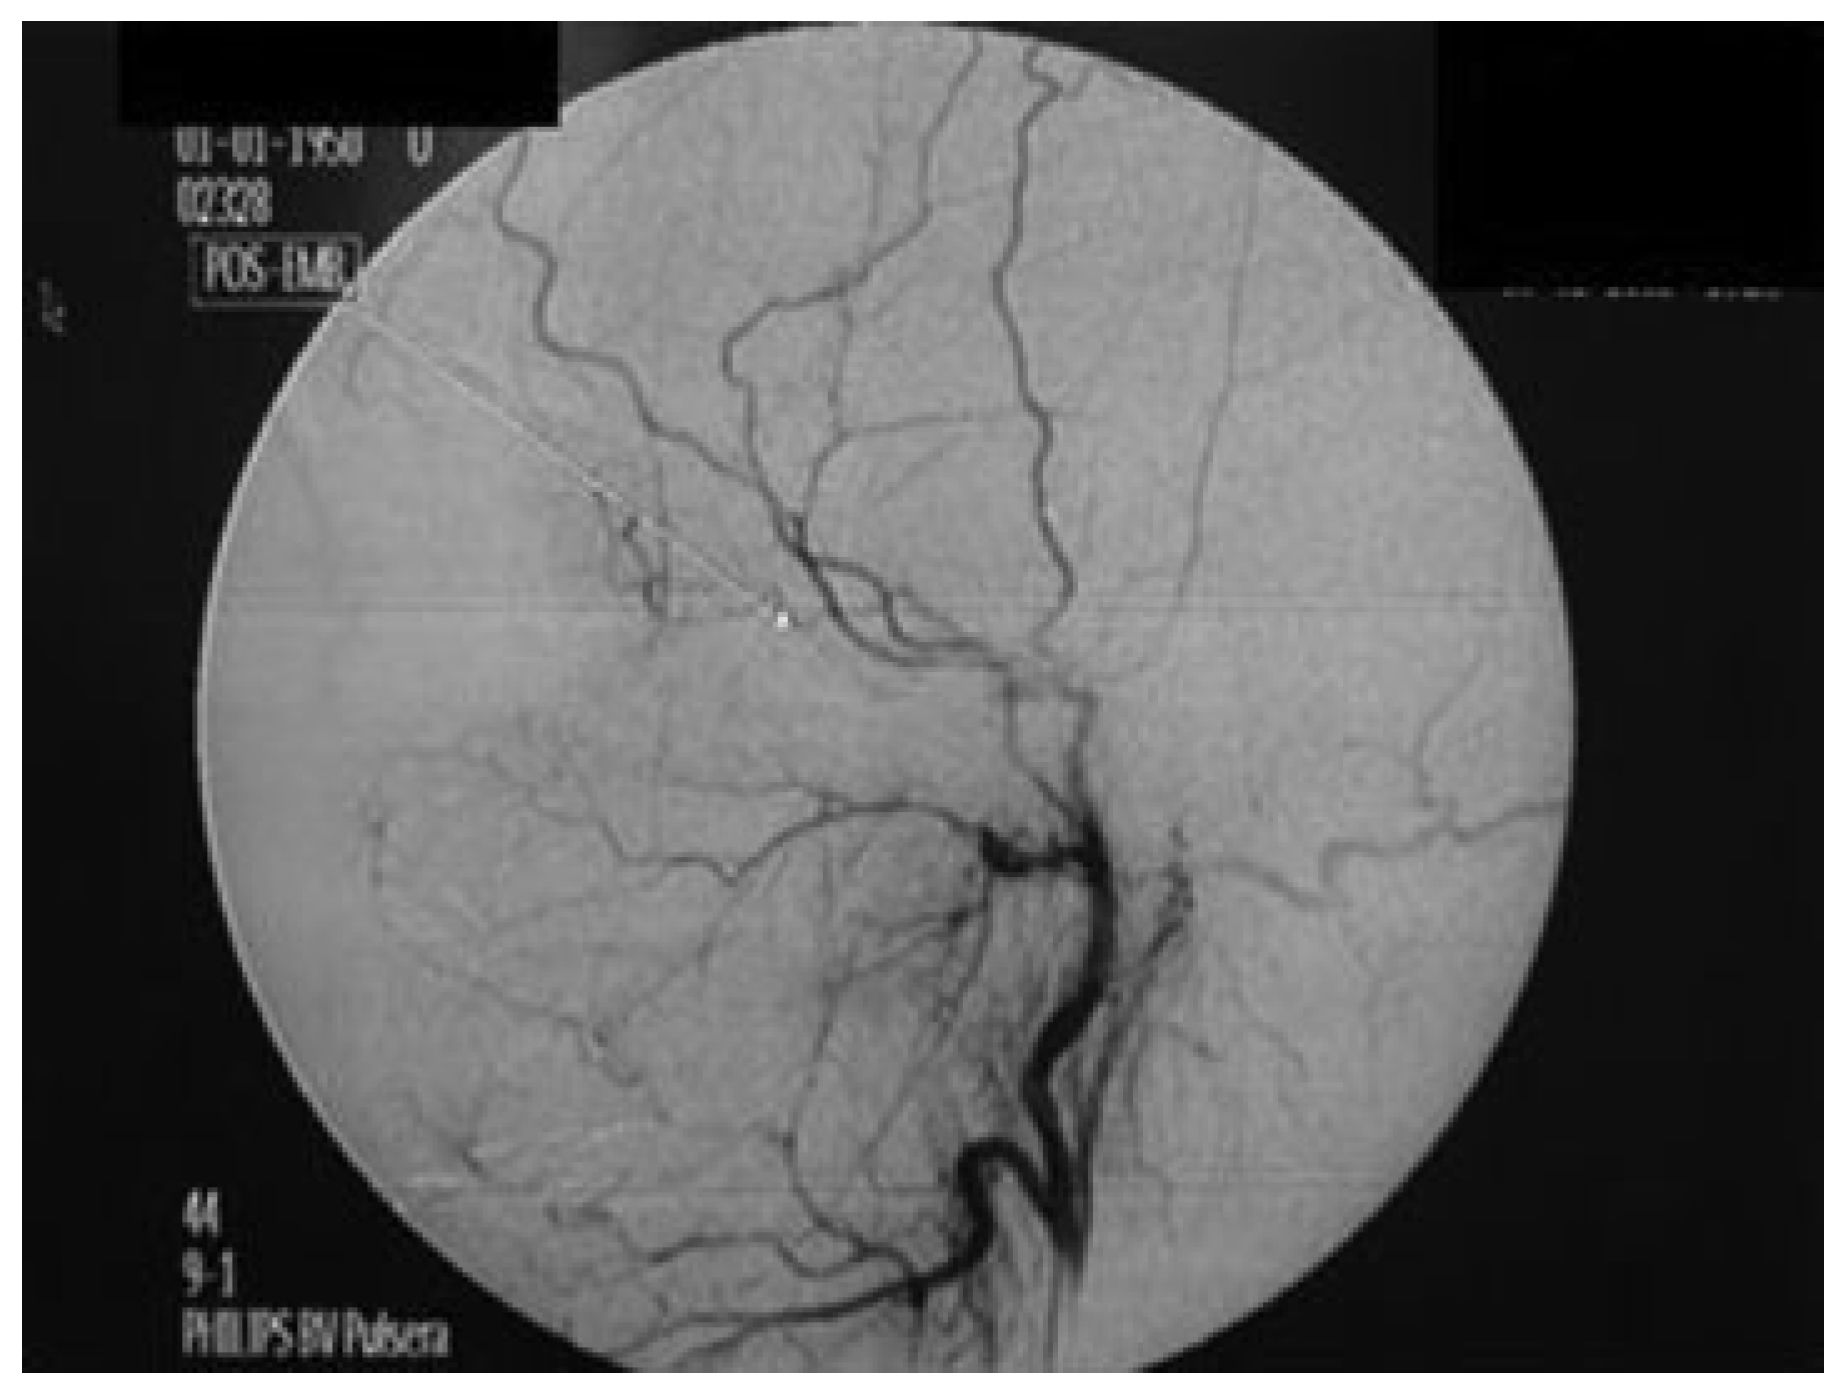

A 22-year-old white woman injured in a car accident in December 2004 was first seen in the Oral and Maxillofacial Surgery (OMS) Department of Batista Memorial Hospital and immediately referred to the General Hospital of Fortaleza (GHF), a level 1 trauma center. She presented edema in the left zygomatic-maxillary region, limited mouth opening, recurrent epistaxis from left nostril at intervals of ~15 days (three previous episodes), left eye divergent strabismus, nonreactive left eye pupil, intact consensual light reflex, normal eye movements, loss of vision, and proptosis in left eye. Physical examination and imaging studies revealed a comminuted fracture of the left zygomatic bone and probable vascular impairment. The patient was evaluated by the specialists in the GHF departments of Oral and Maxillofacial Surgery, Neurology, Ophthalmology, and Endovascular Neurosurgery, and the following studies were requested: arteriography, fundoscopy and magnetic resonance of the orbit, and maxillary sinuses. Results confirmed the diagnosis of pseudoaneurysm of the internal maxillary artery without rupture of the optical nerve. On the same day, after a new episode of epistaxis, the patient was hospitalized in the Emergency Service of GHF to undergo minimally invasive endovascular embolization of the internal maxillary artery. Under local anesthesia, the right femoral artery was punctured with the aid of digital fluoroscopy (Figure 1). Acrylic glue (Histoacryl [1]) was injected by the endovascular neurosurgery and interventional radiology team. Postoperative arteriography revealed instantaneous total regression of the lesion (Figure 2). No bleeding was observed and the edema was substantially reduced on the first day after the procedure. Fifteen days later, the patient returned to treat facial fractures at the OMS Department of HGF, where she has been followed up without any signs or symptoms of the lesion.

Figure 2. Control arteriogram using digital fluoroscopy after embolization of internal maxillary artery (arrow).